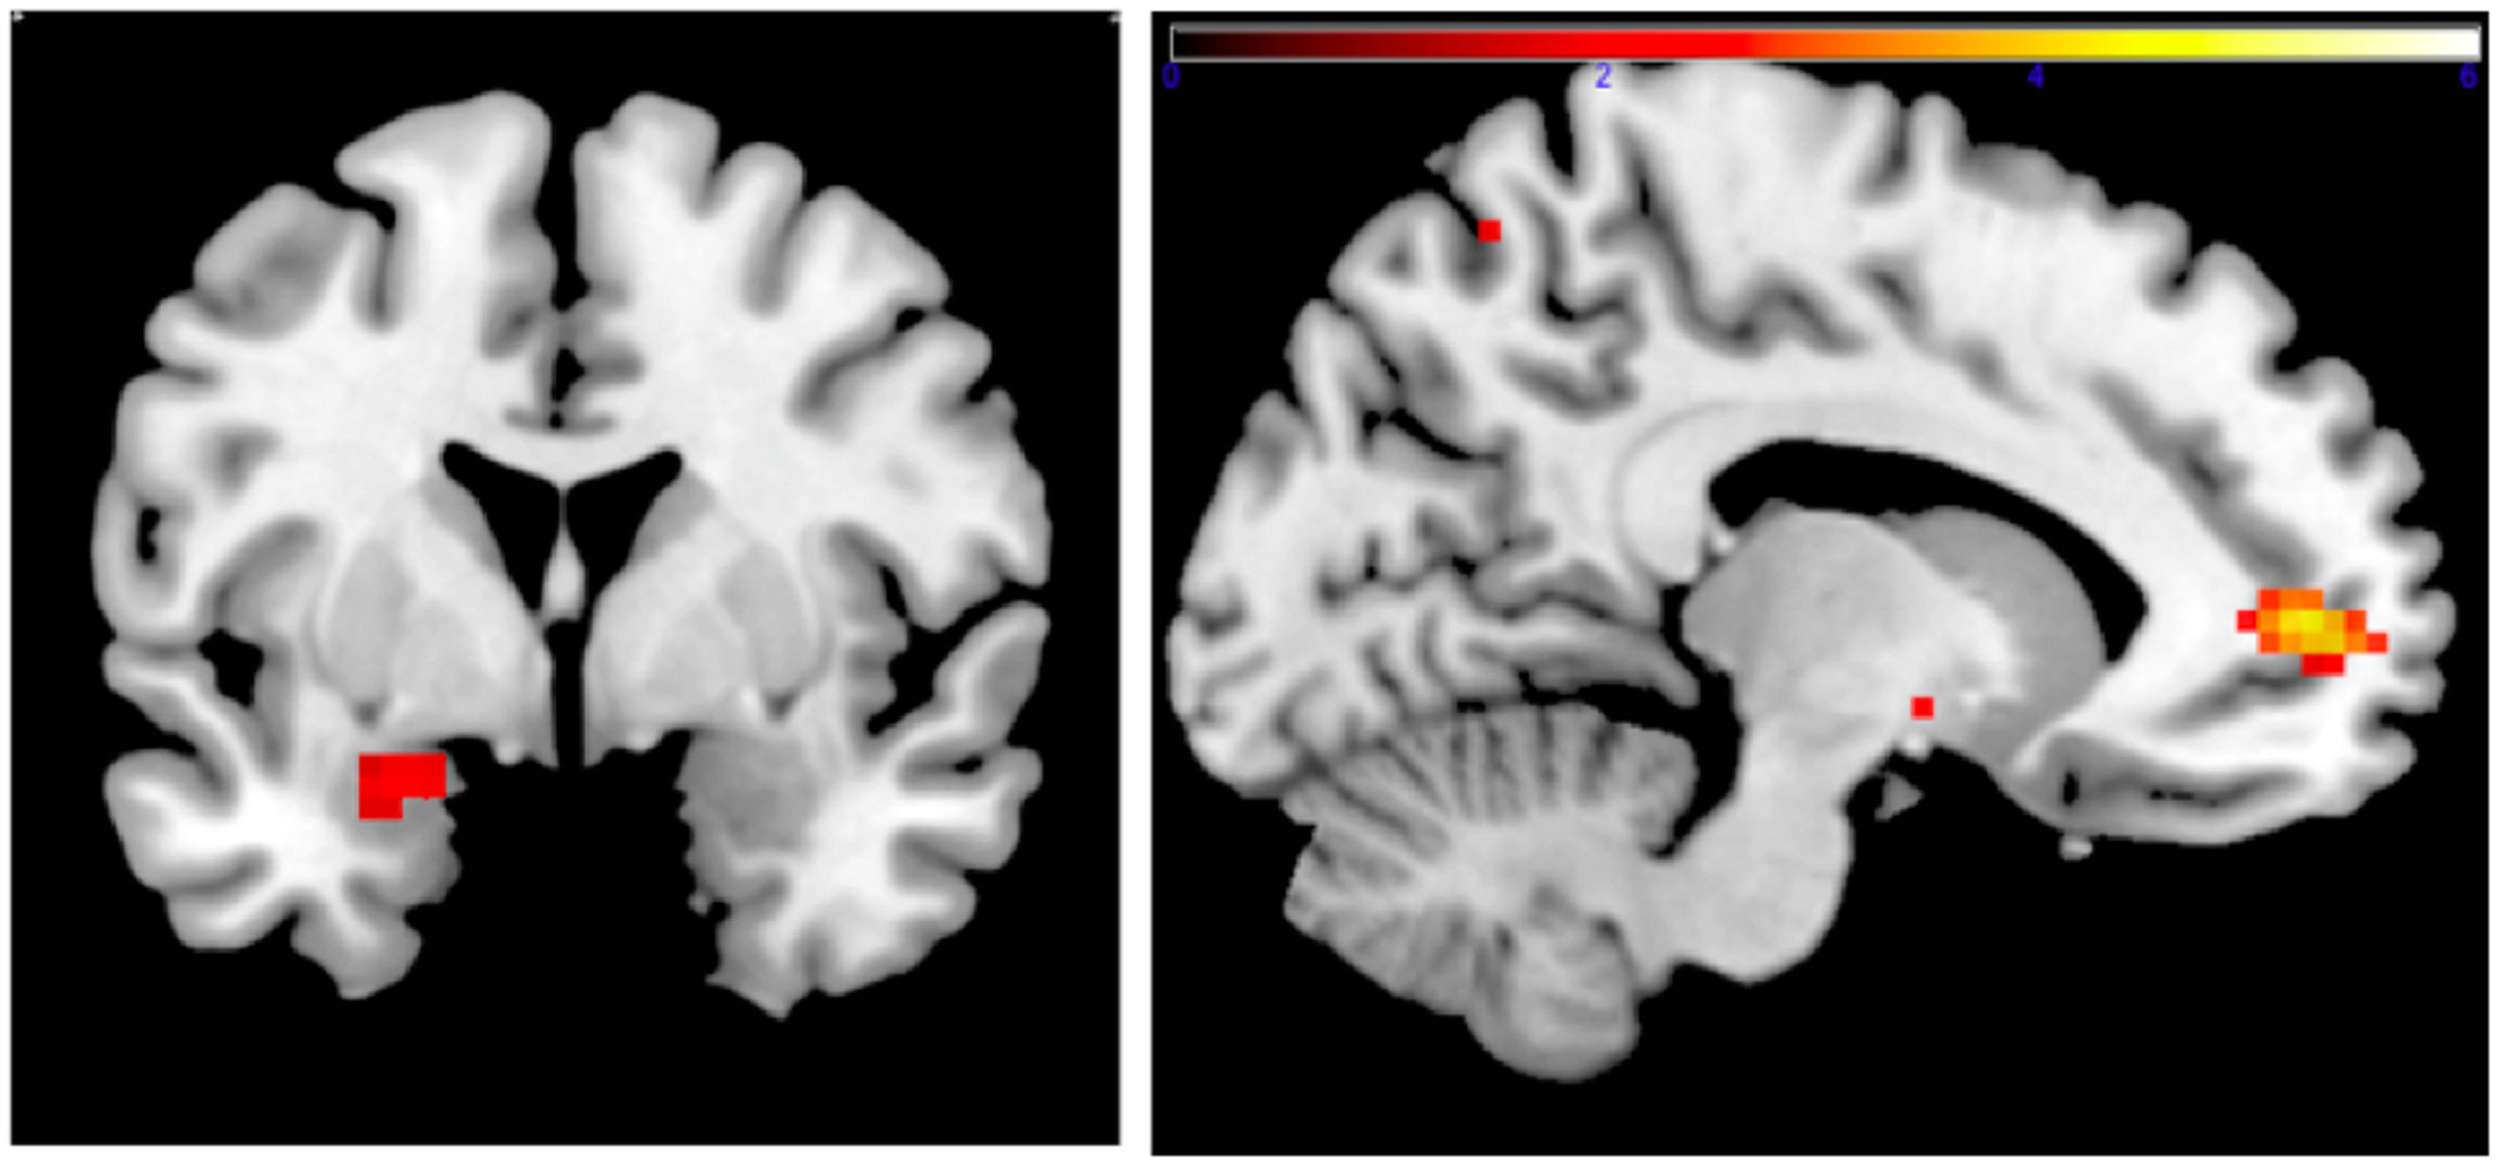

Family income-to-need was negatively correlated with the amygdala activation in contrast threat > happy faces (coordinates: −18, 2, −20; cluster size 11, cluster level FWE-corrected P = 0.036; Z = 3.52). In further exploration, this effect was found to be due to larger activation in Fearful > Happy contrast (see Table 2; Figure 1, left). Family income during childhood explained a substantial portion of the variance of amygdala reactivity to both Fearful faces vs. Shapes (negative correlation of income-to-needs ratio to amygdala activation parameter estimate, R2 = 0.10, P = 0.02), and to Happy faces vs. Shapes (positive correlation of income-to-need to amygdala activation beta, R2 = 0.10, P = 0.02) as shown in Figure 2.

Figure 1. Left: correlation of adult amgydala response to emotional faces with childhood family income. Small volume-corrected left amygdala response in contrast Fearful > Happy faces is negatively correlated with childhood income-to-need ratio. Right: correlation of childhood family income and functional connectivity when viewing emotional faces. Small volume-corrected regression analysis of the connectivity between left amygdala and mPFC in contrast Angry > Happy is in correlation with income-to-need. Correlation is positive (coordinates: −12, 53, 4; cluster size 27, peak level FWE-corrected P = 0.015; Z = 4.14). Same analysis for contrasts Fearful > Happy and Neutral > Happy was not statistically significant.

PPI Analysis

Connectivity between left amygdala (seed region coordinates: −21, −7, −17) and mPFC in the contrast Angry > Happy was positively correlated with childhood income-to-need. Adults with higher income-to-need ratio during childhood exhibited higher amygdala–mPFC connectivity (coordinates: −12, 53, 4; cluster size 27, peak level FWE-corrected P = 0.015; Z = 4.14) (Figure 1, right).